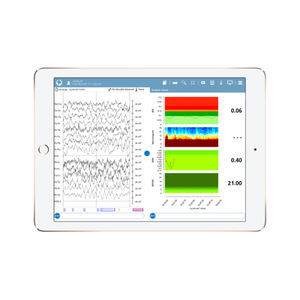

... El monitor de EEG NeuroCenter® está diseñado específicamente para grabaciones de EEG a largo plazo en la UCI y en el quirófano. Combina características distintivas como una interfaz de usuario intuitiva y análisis avanzados de EEG. El uso de la interfaz ...